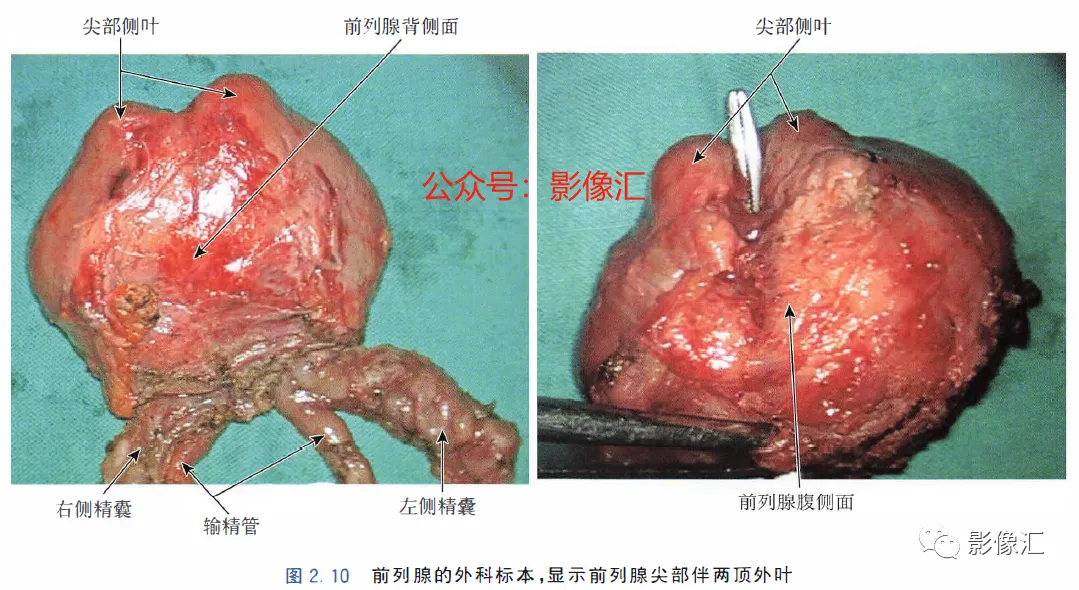

前列腺尖部是用于表示前列腺腺体尾侧(最下方)的术语,与尿道膜部密切接触。前列腺尖部可显示出不同的形态:圆环形或腹侧,背侧或两侧突出(图2. 9和图2.10) ,了解前列腺尖部形态的重要性主要在于两点:(1)前列腺尖部或多或少与EUS(尿道膜部的横纹肌纤维)头侧区域重叠(或覆盖),这些纤维部分融入前列腺尖部(图2.11)。在接受根治性前列腺切除术的患者中,有必要采用能够外翻(exteriorising)和解剖这部分横纹肌纤维的手术技术, 以保持控尿功能(图2.12)。(2)在根治性前列腺切除术中必须避免阳性边缘 。值得注意的是,在尖部水平,腺体组织仅为外周带组织,尖部仅前缘一小部分为AFMS。此外,前列腺尖部构成所谓的梯形区域的顶部,这是众所周知的解剖薄弱区域,在该区域前列腺癌可更易侵犯至前列腺间隙(图2.8)。在其前外侧,前列腺尖部由外括约肌群覆盖,与AFMS及从膀胱颈延伸来的由平滑肌构成的逼尿肌群相融合(图2. 13)。前列腺尖部尾侧与尿道膜部起始部相延续。男性的尿道膜部被认为是位于前列腺尖部和尿道球部之间的尿道部分,长度约为1cm。其内有尿道内括约肌(IUS)和尿道外括约肌(EUS)。IUS从膀胱颈(此处最厚)延伸到尿道球部,沿尾侧方向厚度逐渐减小。IUS环尿道膜部,由双层平滑肌纤维组成,包括内层纵行肌和外部的环形肌(图2. 13和图2. 14)。IUS的神经支配来自自主神经、交感神经和副交感神经系统。下腹下神经丛负责前列腺、前列腺尖部和尿道膜部的所有自主神经支配。其终末支沿内侧走行达耻骨上肌,外侧走行达尿道膜部的EUS,在腹侧构成所谓的阴茎海绵体神经(负责勃起机制)和尿道海绵体神经(负责尿道膜部黏膜的自主神经传入,直接与控尿机制有关(图2 . 13 和图2. 14)。EUS构成横纹肌平面(横纹肌纤维),在尿道膜部水平围绕IUS,在前列腺尖部的前外侧上扩展,并在该水平上构成所谓的EUS围裙(图2. 13)。其肌纤维主要是I 型(即没有肌梭),尽管强度低,但专门负责长时间收缩。EUS的功能在于排尿间期保持尿道腔塌陷,从而防止无意识的尿液渗漏。EUS最厚处位于尿道膜部水平,厚度向头侧逐渐减小,最终构成前列腺围裙。该围裙以Ω(希腊字母“欧米伽”)形围绕尿道膜部,而后正中不包绕, 形成“后正中脊”(图2. 13 和图2. 14)。此外,EUS的部分横纹肌纤维融入到前列腺尖部的下部,位于精阜下方,融入纤维的多少依赖于前列腺尖部形态(图2. 11) 。EUS的神经支配和动脉供血分别来自外阴神经和外阴内动脉。该神经为躯体神经,因此EUS可随意控制。外阴内神经和动脉均向头侧走行,至会阴深横肌处,发出分支支配EUS最尾侧部分,随后形成阴茎背侧神经脊背侧动脉。前列腺尖部与支配EUS的外阴内动脉的分支之间距离为3~13mm (图2. 13)。IUS和EUS构成所谓的控尿被动及内在因素。它们的功能基本上是“塌陷”尿道至“后正中脊”,这样可防止排尿间期无意识的尿液“泄露”(图2.11和2.13)。阴茎海绵体神经在前列腺周围筋膜的后外侧及前外侧走行。手术操作时保留这些外侧神经对于确保前列腺根治术后勃起功能的恢复是至关重要的。会阴体是一纤维肌性结构,难以在解剖上进行评估,其功能是支持所有构成会阴部及支撑盆腔脏器的肌肉及腱膜结构。对于控尿,会阴体形成一固定的底盘,通过将EUS的横纹肌平面压至底盘处,从而可使EUS正确发挥功能,这样在排尿间期可以正确地使尿道塌陷。会阴体由以下结构组成(图2.13)和图2.14)。